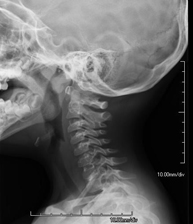

- RX Columna cervical

Tècnica que usa els raigs X a través de la qual s'obtenen imatges de la columna cervical per al seu estudi. Indicacions: traumatisme, contractura cervical, dolor articular. - RX Ossos propis nasals

Tècnica que usa els raigs X a través de la qual s'obtenen imatges de la columna cervical per al seu estudi. Indicacions: traumatisme, dolor cervical. - RX Columna dorsal